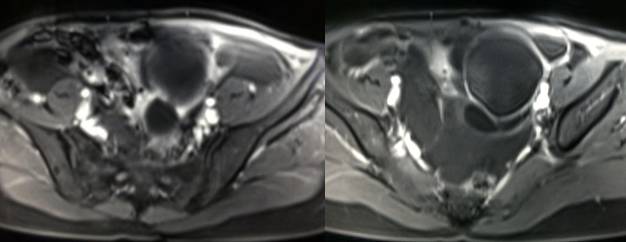

MR检查:

病理结果:黄体血肿

黄体血肿早期:囊内出血较多时,表现为卵巢内近圆形囊肿,囊壁厚,内壁粗糙。

黄体血肿中期:黄体血肿内血液凝固,部分吸收,囊壁变薄而,内壁光滑。

根据时间不同MR信号也有所不同,TIWI脂肪抑制序列可以鉴别脂肪和出血。

卵巢囊肿:呈均匀的T1WI 低信号,T2WI 高信号,边界清楚,壁薄,大多数病灶直径≤5 cm,但囊肿的起源及定性诊断困难。

功能性囊肿:因囊肿内容物成分不同,信号可有改变,随访观察数月后其信号和大小可出现变化或消失。

炎性假囊肿:囊壁可强化,周围有粘连。

卵巢囊腺瘤:呈囊性或囊实性肿块,边界清楚,壁厚,有分隔或结节( 直径≤3mm) ,浆液性囊腺瘤:囊液呈T1WI 低信号,T2WI 高信号,黏液性囊腺瘤呈T1WI 高信号、T2WI 稍高信号,T2WI 信号高于水,信号较均匀,增强扫描囊壁及壁结节强化。

畸胎瘤:多呈囊性或囊实性,单房或多房状,囊内液体可有分层,实质由多胚层组织构成,MR 信号不均,肿块内见脂肪信号有利于畸胎瘤的诊断。

巧克力囊肿:常呈多发的单囊或多囊改变,病灶大小不等,囊壁厚薄不均,囊内信号复杂,囊内或各囊腔间血液因出血时期不同,信号常呈多样性,囊肿内反复出血、破裂,形成相互粘连的多房性囊肿,是其较为特征性的表现。

在鉴别卵巢畸胎瘤、出血性囊肿或巧克力囊肿时,MR 脂肪抑制T1WI 可明确肿块内高信号成分是脂肪还是出血,同时由于脂肪组织与非脂肪组织的共振频率不同,在两者交界处沿磁场频率编码方向出现化学位移伪影,但出血性囊肿与巧克力囊肿的鉴别有时较为困难。